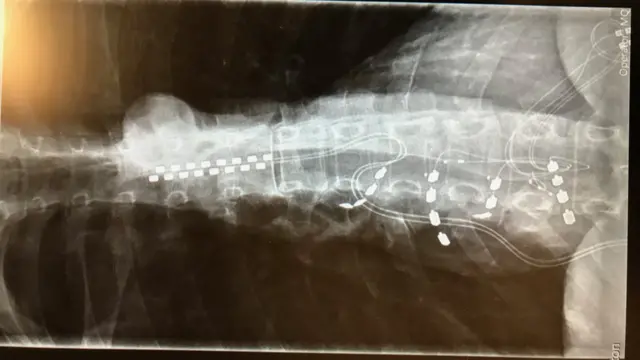

El equipo de Southampton le colocó un implante de estimulación a lo largo del nervio espinal, pero solo le redujo el dolor en un 50%.

Alison se sometió a 20 procedimientos para implantarle más electrodos, y también para corregir los cables que habían salido de su lugar.

También tuvo que llevar un corsé durante dos años para tratar de mantener los cables donde correspondía.

Su cuerpo, con unas articulaciones hipermóviles, no conseguía mantener los electrodos en su lugar.

En un último intento para liberarla del dolor, el doctor Vajramani le insertó un implante, combinado con un estimulador de la médula espinal, para crear un modelo híbrido.

Se lo implantaron en dos operaciones en diciembre de 2018.